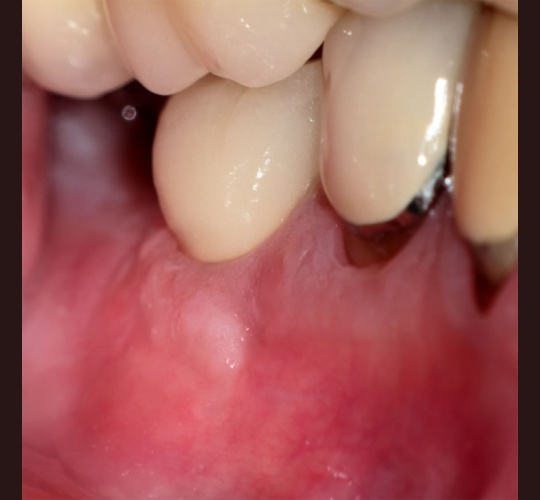

Implants: Case #8

Patient presented with a sinus tract, the radiograph showed apical resorption on distal root. The tooth was extracted and the mesial root socket was grafted allowed to heal for 4 months and a Straumann tissue level implant was placed. 8 weeks later the crown was placed.